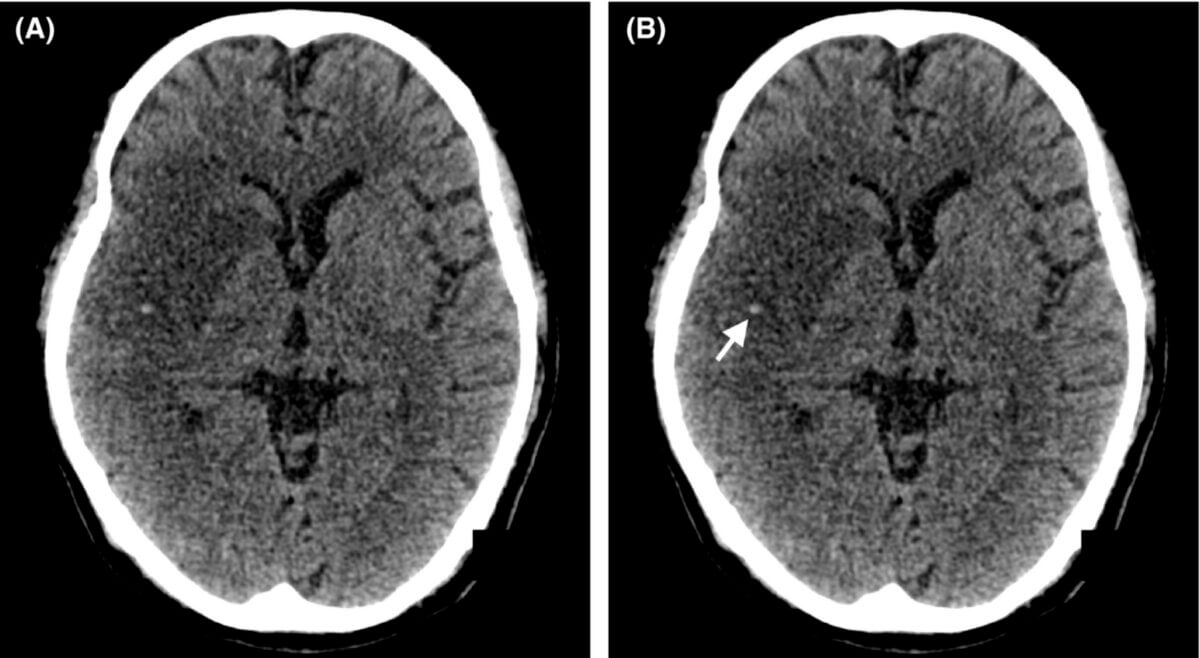

Das MCA-Punkt-Zeichen ist ein radiologisches Zeichen, das auf eine thromboembolische Okklusion der distalen Äste der Arteria cerebri media (MCA, ACM) hinweist. Er erscheint als punktförmige Hyperdensität in der Sylvischen Fissur auf axialen, nativen CT-Bildern des Schädels. Dieses Zeichen ist ein früher Indikator für einen akuten ischämischen Schlaganfall im Versorgungsgebiet der Arteria cerebri media.[1]

- Lokalisation: Hyperdensität im M2- oder M3-Segment der MCA innerhalb der Sylvischen Fissur

- Erscheinungsbild: auf axialen CT-Bildern erscheint die thrombosierte Arterie als hyperdenses, punktförmiges Areal – daher der Name "dot sign"

- Differenzierung: Im Gegensatz zum hyperdensen Mediazeichen, das eine lineare Hyperdensität im M1-Segment der MCA darstellt, betrifft das MCA-Punkt-Zeichen die distalen Segmente und erscheint punktförmig